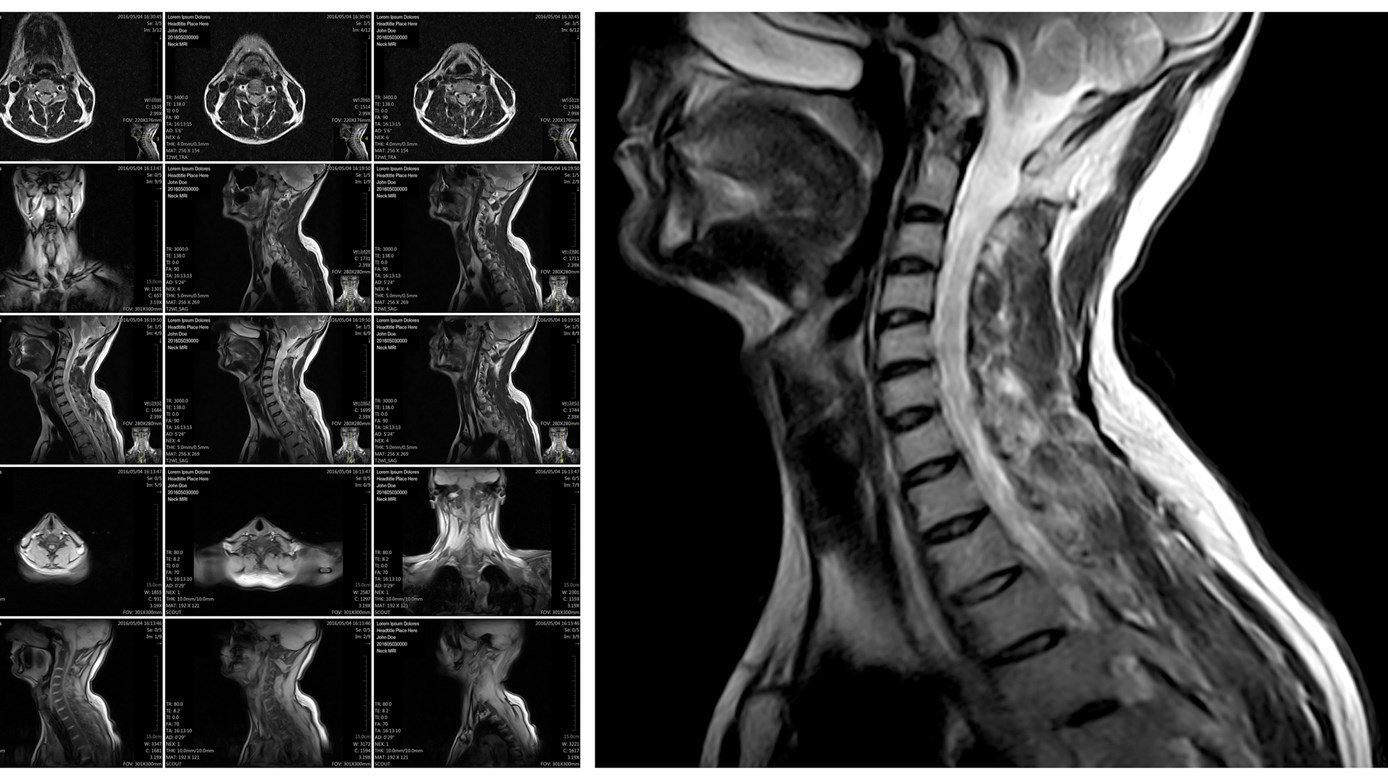

The patient has an injury to the cervical spine, lumbar spine or knee that meets the criteria outlined in the MRI Clinical Pathways.

- Cervical Spine diagnostic imaging pathway